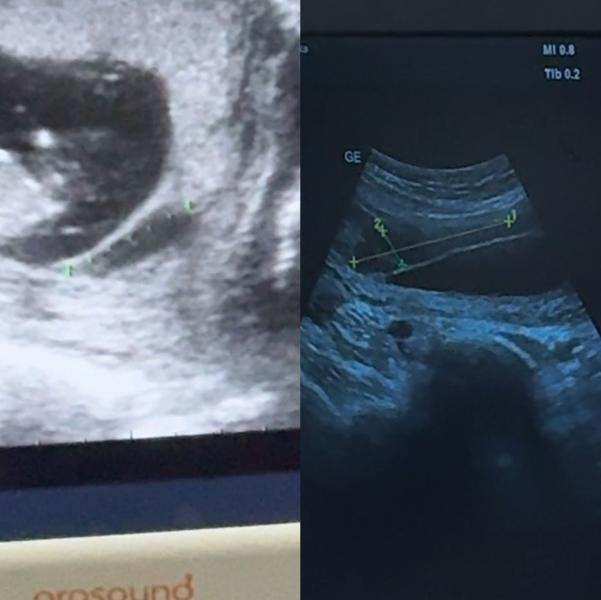

Три дня назад были на УЗИ, конечно хотелось бы услышать что у вас все хорошо, живите спокойно нервная мамаша.

У меня низко расположена плацента.

И пятый день тянет живот.

Начнем с хорошей, я наконец то дождалась приема своего гинеколога и узнала, что все риски у меня низкие, по крови первого скрининга все прекрасно и хорошо. (1 фото)

По не очень хорошей новости, я уже писала, что гематома у меня увеличилась, была на 12 недели 3 см на 8 мм стала, 7,4 см на 1,5 см гинекологу это очень не понравилось, сказали переделать узи на следующей недели и если все остается так же, то госпитализация в стационар, что бы быть...